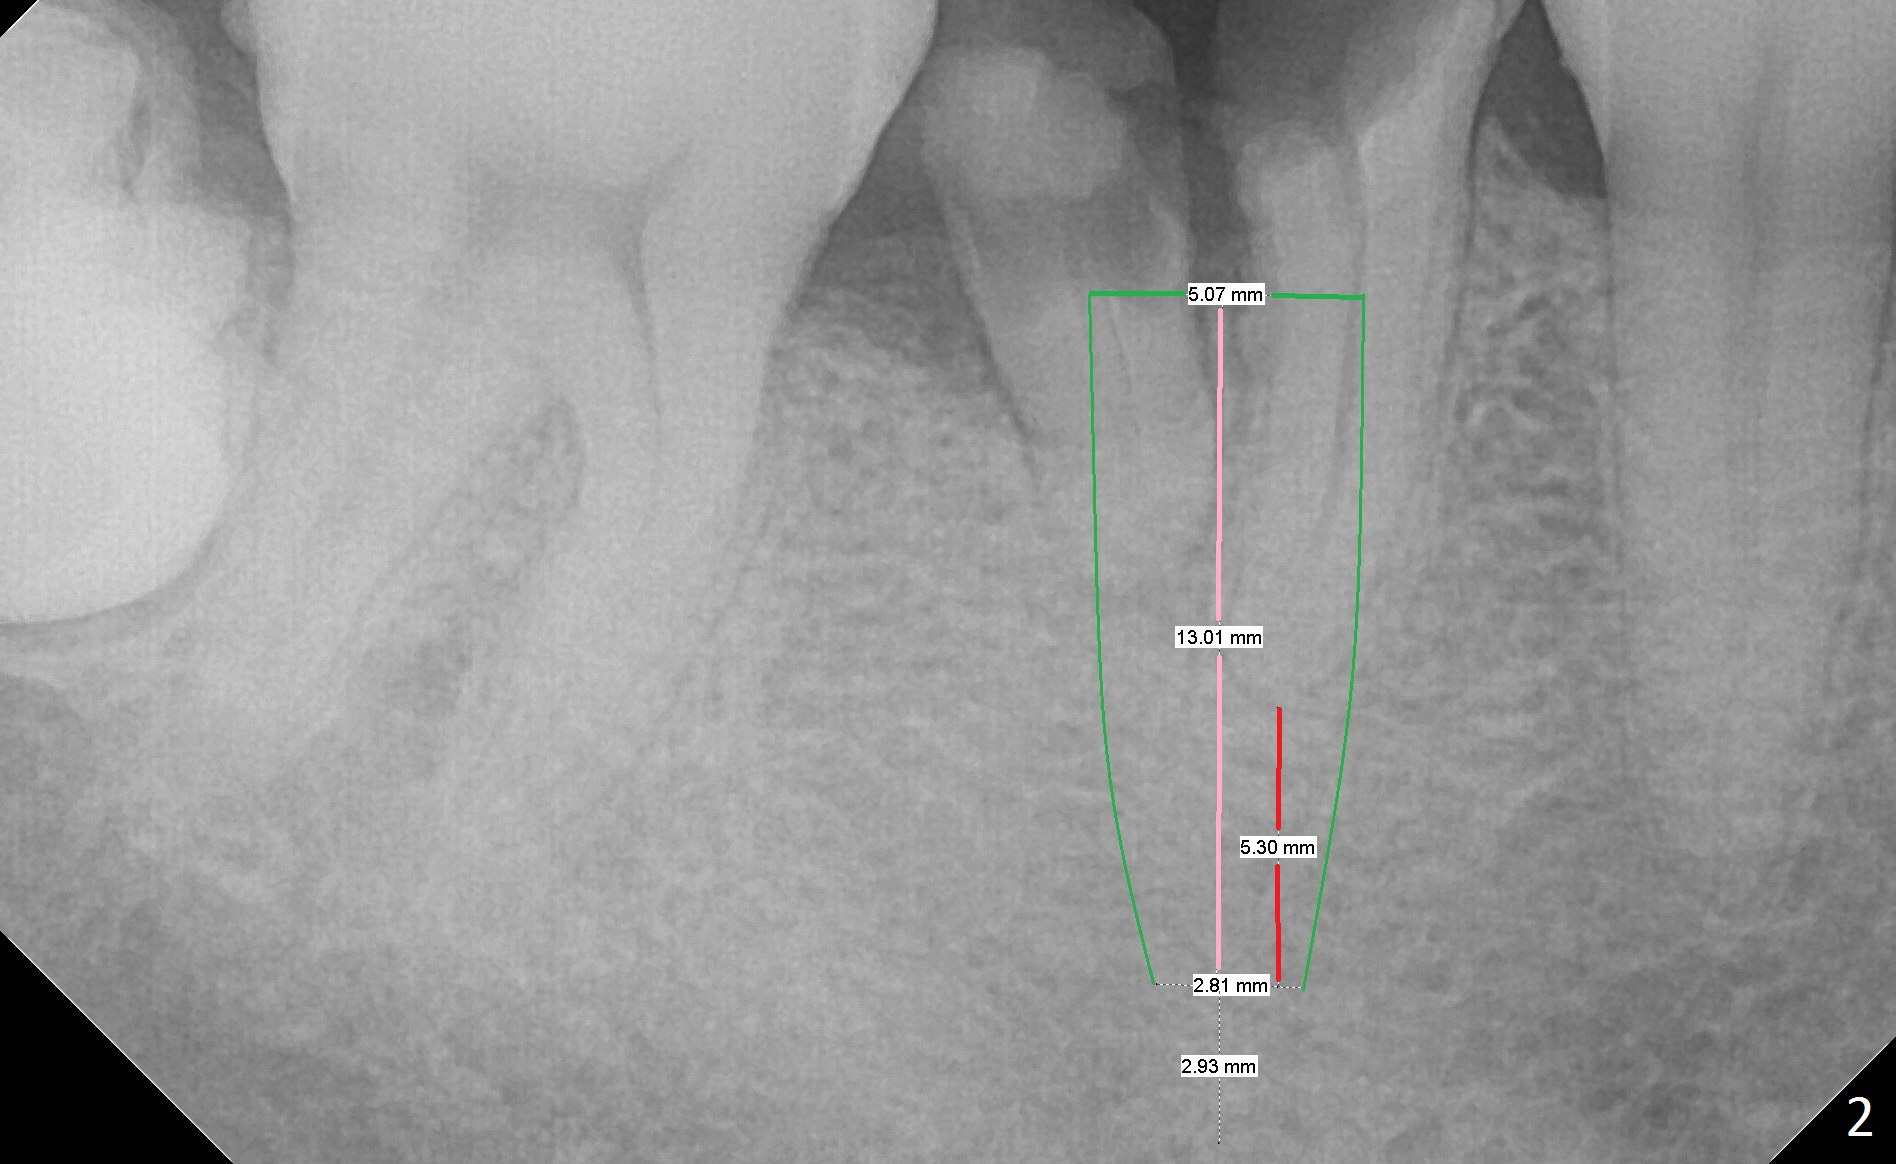

A 43-year-old man has residual roots at #30 (Fig.1). The mesial (M) and distal (D) roots approximates each other so close that the septum is thin (Fig.1,3-5). The latter is unfavorable for osteotomy. After extraction (Fig.5), the middle of the septum (Fig.8a (axial section of the sockets)) will be sectioned (Fig.6, 8b,c) prior to initial osteotomy (Fig.7,8d). The depth of the latter will be ~ 5 mm (Fig.2 red line) for a 13 mm (pink line) IBS implant.